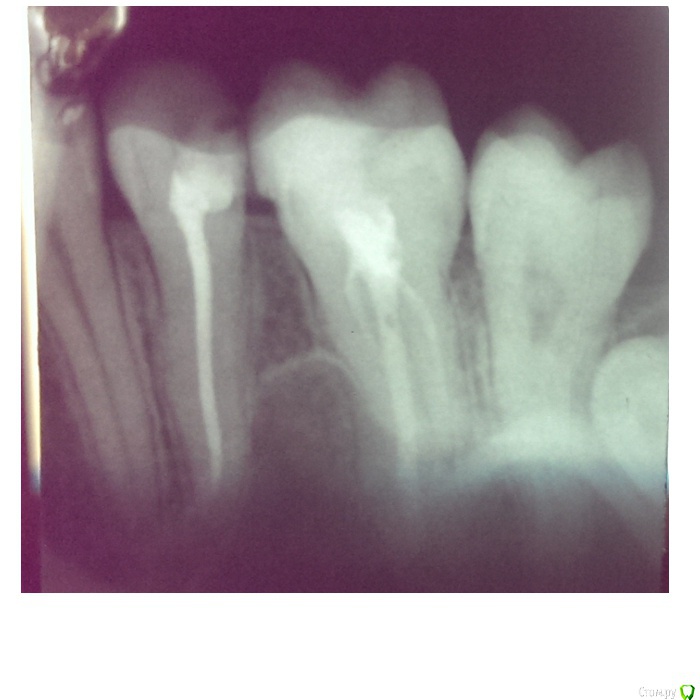

НинаД Опубликовано 23 ноября, 2015 Поделиться Опубликовано 23 ноября, 2015 Здравствуйте. На 25 зубе удалили нерв, установили пломбу. Две недели зуб ныл, при жевании довольно сильно болел. Обратилась к стоматологу, она отправила на рентген. Посмотрев снимок, врач сказала, что пломба установлена идеально, но есть небольшой карман, из-за него может возникать боль. В итоге мне вкололи линкомицин и выписали препарат «Аркоксиа». Через несколько часов после укола я пила прохладное молоко и в районе больного зуба возникла очень сильная боль. Спустя пару дней ситуация такая: зуб слабо ноет, при надавливании немного болит, на постукивание реагирует (боль не сильная) и десна вокруг него красная. Меня беспокоит реакция зуба на холодное, очень резкая боль возникает. 24 зуб тоже реагирует на постукивание и десна вокруг него тоже красная. Из-за чего могут возникать подобные боли? Может быть боль возникает не от холодного, а от жидкости попадающей в этот карман? Ссылка на комментарий

diesel87 Опубликовано 23 ноября, 2015 Поделиться Опубликовано 23 ноября, 2015 В этом зубе 2 корня, следовательно минимум 2 канала, как вариант пролечили и запломбировали только 1 канал. Кармана нет, но есть нависающий край пломбы на 26 зубе, из-за которого впоследствии как раз и может образоваться карман. Ссылка на комментарий

St. Опубликовано 23 ноября, 2015 Поделиться Опубликовано 23 ноября, 2015 Явного кармана на снимке не вижу. Ссылка на комментарий

Гарриевич Опубликовано 24 ноября, 2015 Поделиться Опубликовано 24 ноября, 2015 На счет двух каналов не согласен, это 5ка, там в большинстве случаев один щелевидный канал. То, что Вам кололи линкомицин говорт о неадекватном пониманиипроцессов в полости рта. Попробуйте обратиться к другому специалисту Ссылка на комментарий

diesel87 Опубликовано 24 ноября, 2015 Поделиться Опубликовано 24 ноября, 2015 На счет двух каналов не согласен, это 5ка, там в большинстве случаев один щелевидный канал. То, что Вам кололи линкомицин говорт о неадекватном пониманиипроцессов в полости рта. Попробуйте обратиться к другому специалистуПо снимку же видно 2 корня, допускаю конечно что они могут сходить в один. Ссылка на комментарий